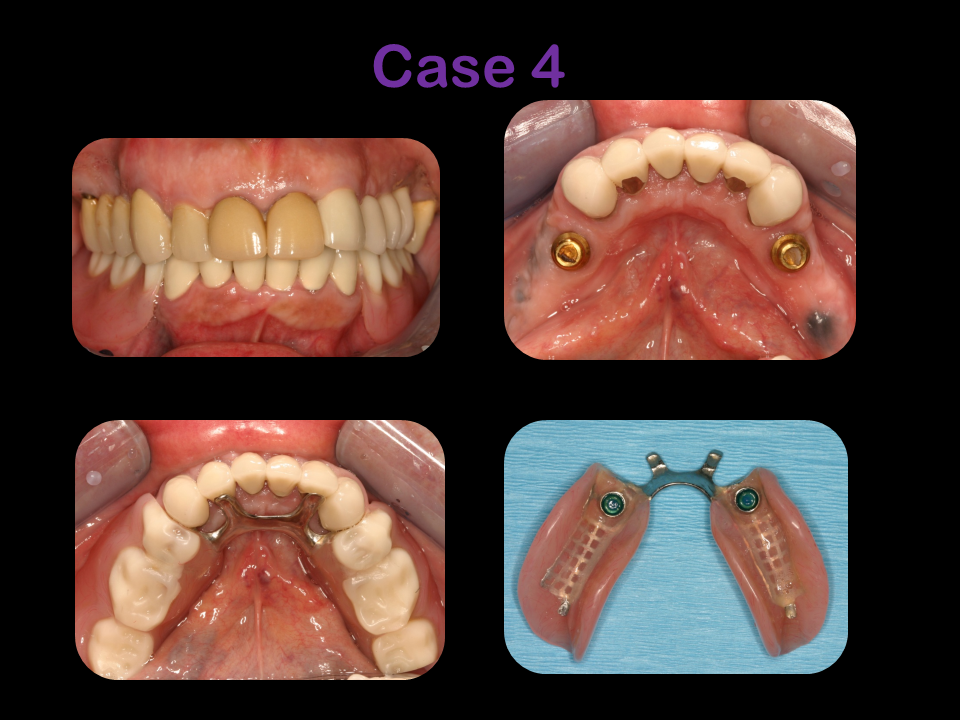

Explore the artistry and precision of Dr. Feldner’s 32 years of expertise through our photo gallery, showcasing the remarkable transformations in periodontics, implantology, and bone grafting. Each before-and-after photo is a testament to Dr. Feldner’s commitment to excellence, reflecting a mastery that blends innovative techniques with a passion for restoring smiles and health.